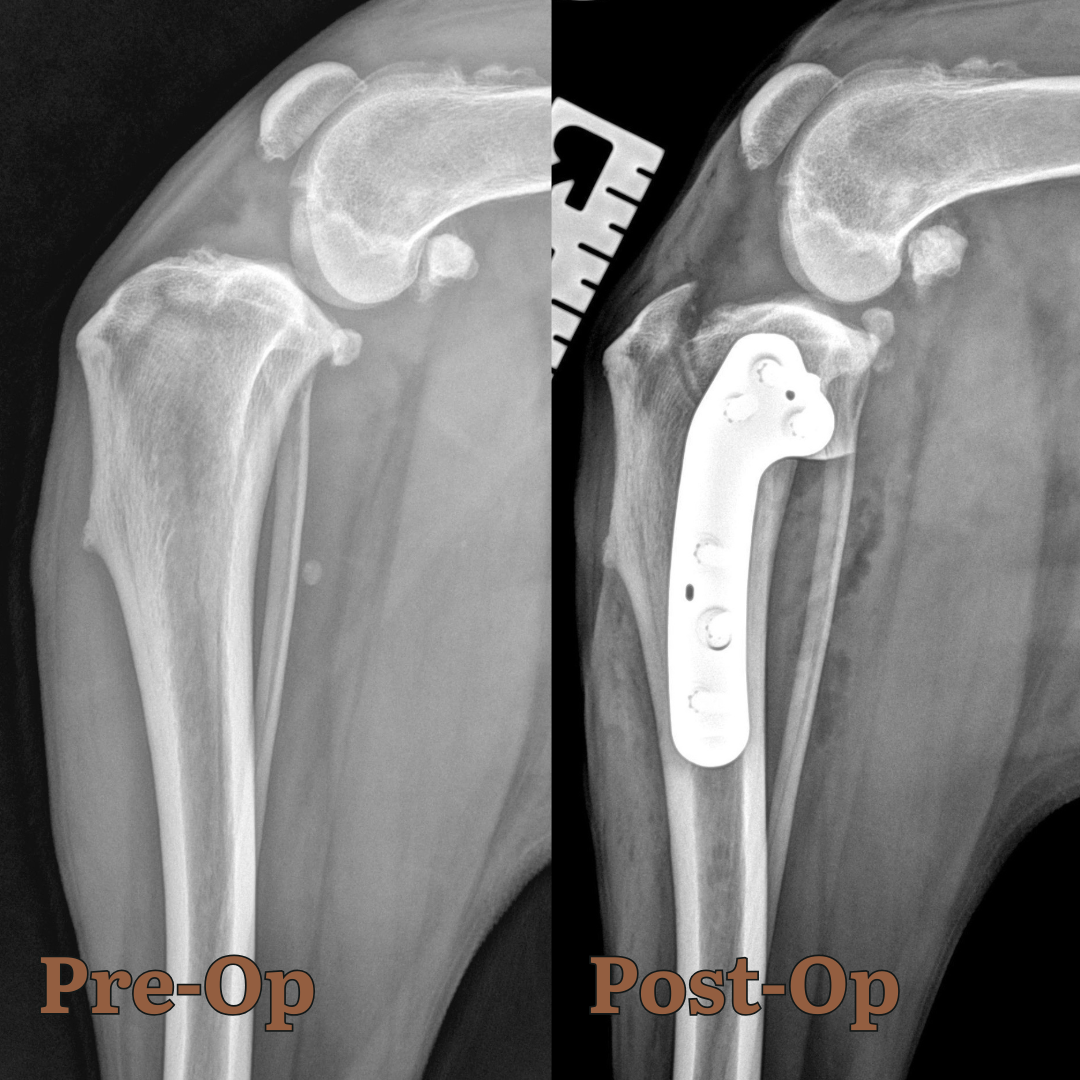

During the TPLO surgery we explore the stifle (knee) joint and address any meniscal problems, then we make a cut in the top of the tibia with a special saw blade and rotate the segment and finally secure it with a specially designed TPLO plate and screws. Postoperative radiographs are taken to confirm appropriate placement of implants. We also inject a long-acting lidocaine to help with pain.